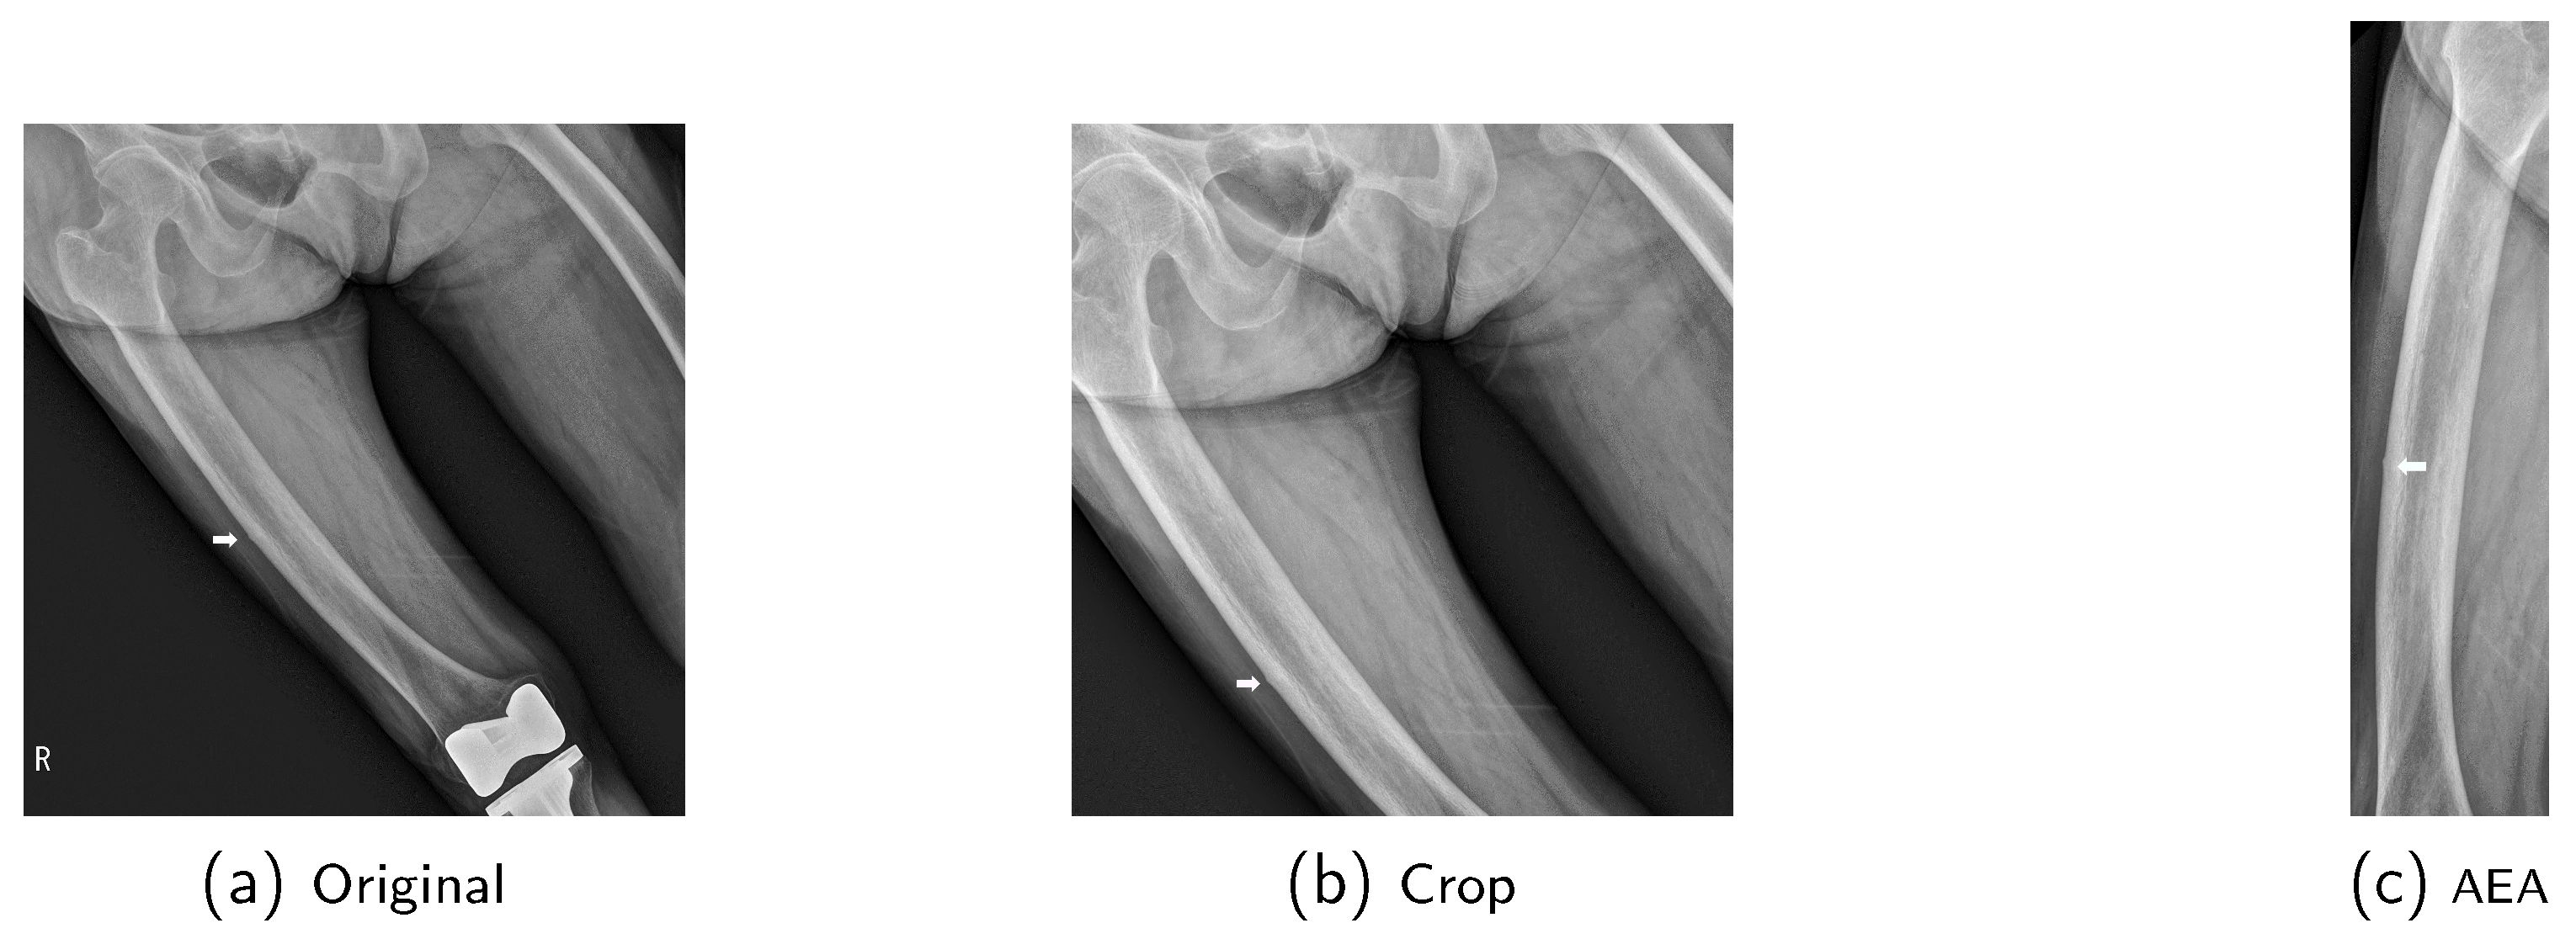

To enhance the data processing efficiency and optimize memory usage, we converted Digital Imaging and Communication in Medicine (DICOM) files into Numerical Python (NumPy) format. The data were then preprocessed using two different methods (Figure 6). (1) Crop (C): To reduce unnecessary information in the image, such as left/right markers and knee implants, we cropped the images to a size of 2200 × 2200, corresponding to the smallest data dimension. To preserve S-IAFF characteristics, only the bottom portion of the images was cropped for height, while both sides were symmetrically cropped for width. (2) Automated Extraction and Alignment (AEA): We employed a segmentation model to generate femur masks from the original X-ray images. After evaluating several models, U-Net++ was selected for its superior performance. To further refine the masks, the connectivity of pixel values in the generated mask was computed to eliminate noise, and the inlier set was extracted using the RANdom SAmple Consensus (RANSAC) algorithm [67]. The Hough transform [68] was then applied to determine the rotation angle for vertically aligning the mask. Additionally, the histogram was analyzed to exclude the knee and pelvis regions, ensuring that only the RoI of the femur was extracted from the mask. After preprocessing, the (C) images were resized to 1024 × 1024, and the (AEA) images were resized to 1024 × 256 using bilinear interpolation. Finally, the pixel values were normalized to the range [0,1].